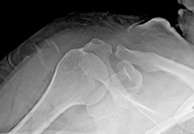

석회성건염 수술 전